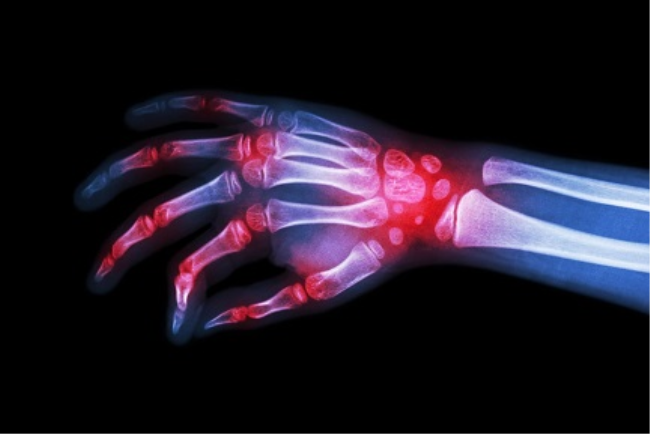

ראומטולוגיה היא מומחיות ברפואה העוסקת באבחון ובטיפול של מחלות אוטואימוניות ודלקתיות הפוגעות בעיקר במערכת השלד והשרירים שבגוף - במפרקים, בשרירים, בגידים וברצועות. הפרעות ראומטולוגיות עלולות להשפיע גם על כלי הדם, העור, העצבים והאיברים הפנימיים .

מחלות ראומטולוגיות הוא מונח המאגד בתוכו למעלה מ -150 מחלות ותסמונות, שלרוב מתקדמות ככל שעובר הזמן, והן מלוות בכאב . סוגים נפוצים של מחלות ראומטולוגיות כוללים, בין היתר, דלקת מפרקים שגרונית, דלקת מפרקים ניוונית, פיברומיאלגיה, שיגדון (Gout), זאבת ועוד. כל אחת ממחלות אלו נפוצה באוכלוסייה שונה, למשל דלקת מפרקים ניוונית וזאבת נפוצות יותר בנשים, בעוד ששיגדון נפוצה יותר בגברים . בעולם תוכן זה תוכלו למצוא מגוון מידע על ראומטולוגיה, כגון מה זה ראומטולוגיה, מחלות ראומטולוגיות, סימפטומים נפוצים ועוד.